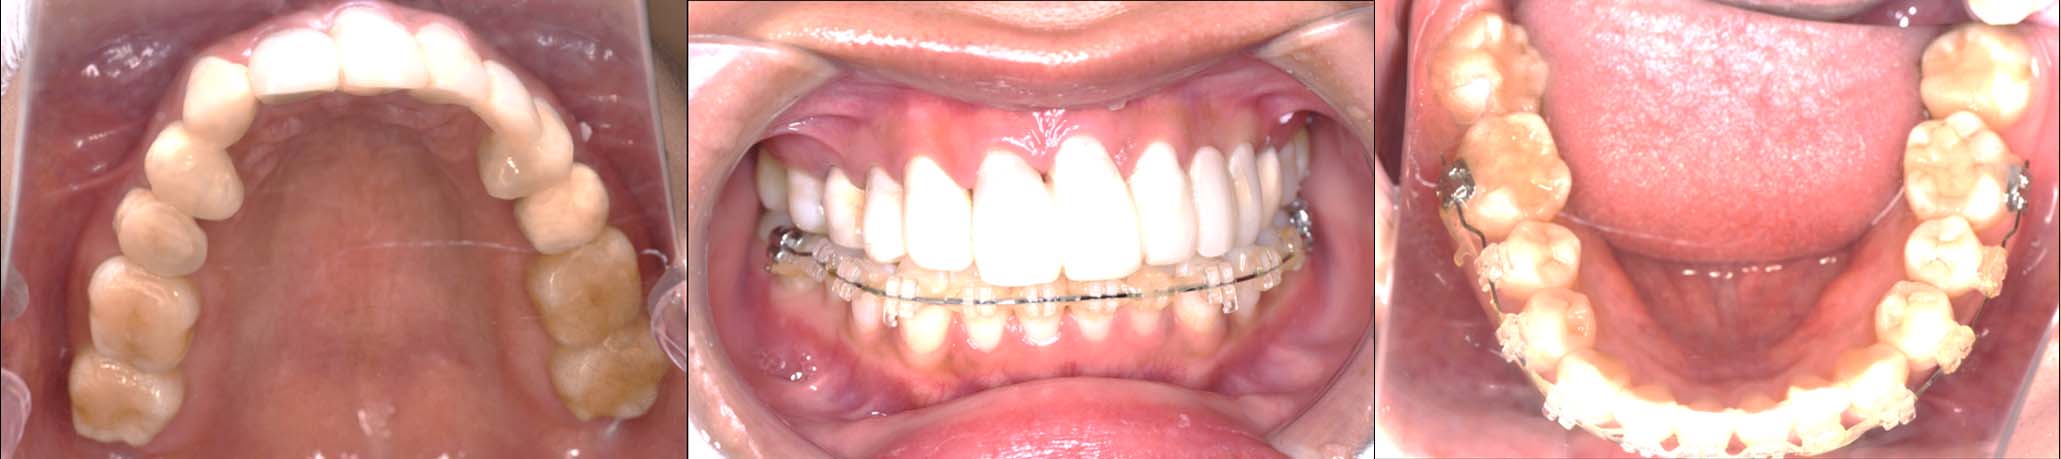

⑤2024年5月 上顎前歯部8本へ仮歯(TEK)

を装着

2024年 10月 下顎MTM開始

2025年 12月25日